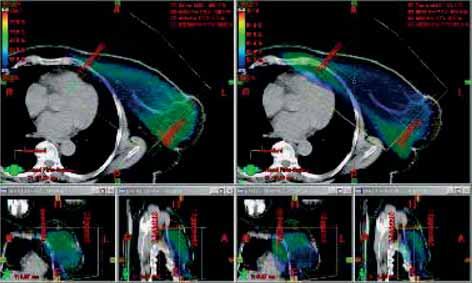

- Podle rozměrů pacientky volit vyšší energii X záření pro

tangenciální pole (u velké vzdálenosti mezi CP tangenciálních poli

22 cm a více) nebo i u axillárního pole (příliš hluboké PTV): např.

6X + 18X nebo 6X + 6X technika pole v poli nebo 18 X (zvážit

použití bolusu). (obr. 3a, b, c, obr. 4a, b).

Obr. 4a Optimalizace RT tangenciální pole X záření en. 6 MV s MLC a bez MLC

Obr. 4b Optimalizace RT X záření en.18MV+ 6MV tg pole s MLC a bez MLC